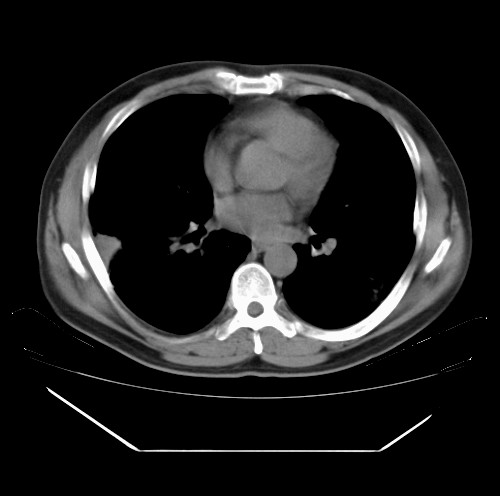

标题: CT22085:双肺多发结节

男,44岁,咳嗽,痰中带血2天。

除肺内及胸膜下可见多发大结节外,在肺小叶中心核、小叶间隔及支气管血管束上亦可见多方小结节,可以认为是随机分布。考虑转移可能性大。

仔细观察病灶形态,病灶边界部分清楚,结合临床症状,首先考虑转移,纵隔内多个肿大淋巴结影。

双肺血管纹理末端多发类圆形结节,边界光滑清晰 气管前腔静脉后淋巴结肿大

考虑转移瘤

本例双肺多发类圆形高密度灶,边清,结合病史多考虑双肺多发转移改变,可以结合实验室检查。